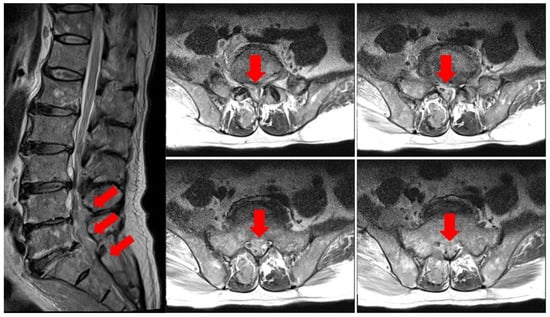

At the time of admission to the Hematology Oncology Department, an MRI of the lumbar spine showed suspicious findings of multifocal bone metastasis in the thoracic-lumbar spine, including T11-L5 and bilateral sacrum, iliac bones and epidural metastasis at L4/5, L5/S1 and the sacrum (Figure 1). PET-CT was also performed after the third R-CHOP at the time of admission to the Department of Hematology and Oncology, and showed residual hypermetabolic lesions in L5, the sacrum, and the right presacral area (Figure 2). Electrodiagnostic examination was performed five months after the onset (Table 1).

Figure 1. Lumbar spine MRI T2 weighted image. Epidural metastasis at L4/5, L5/S1, and the sacrum is noted (arrows).